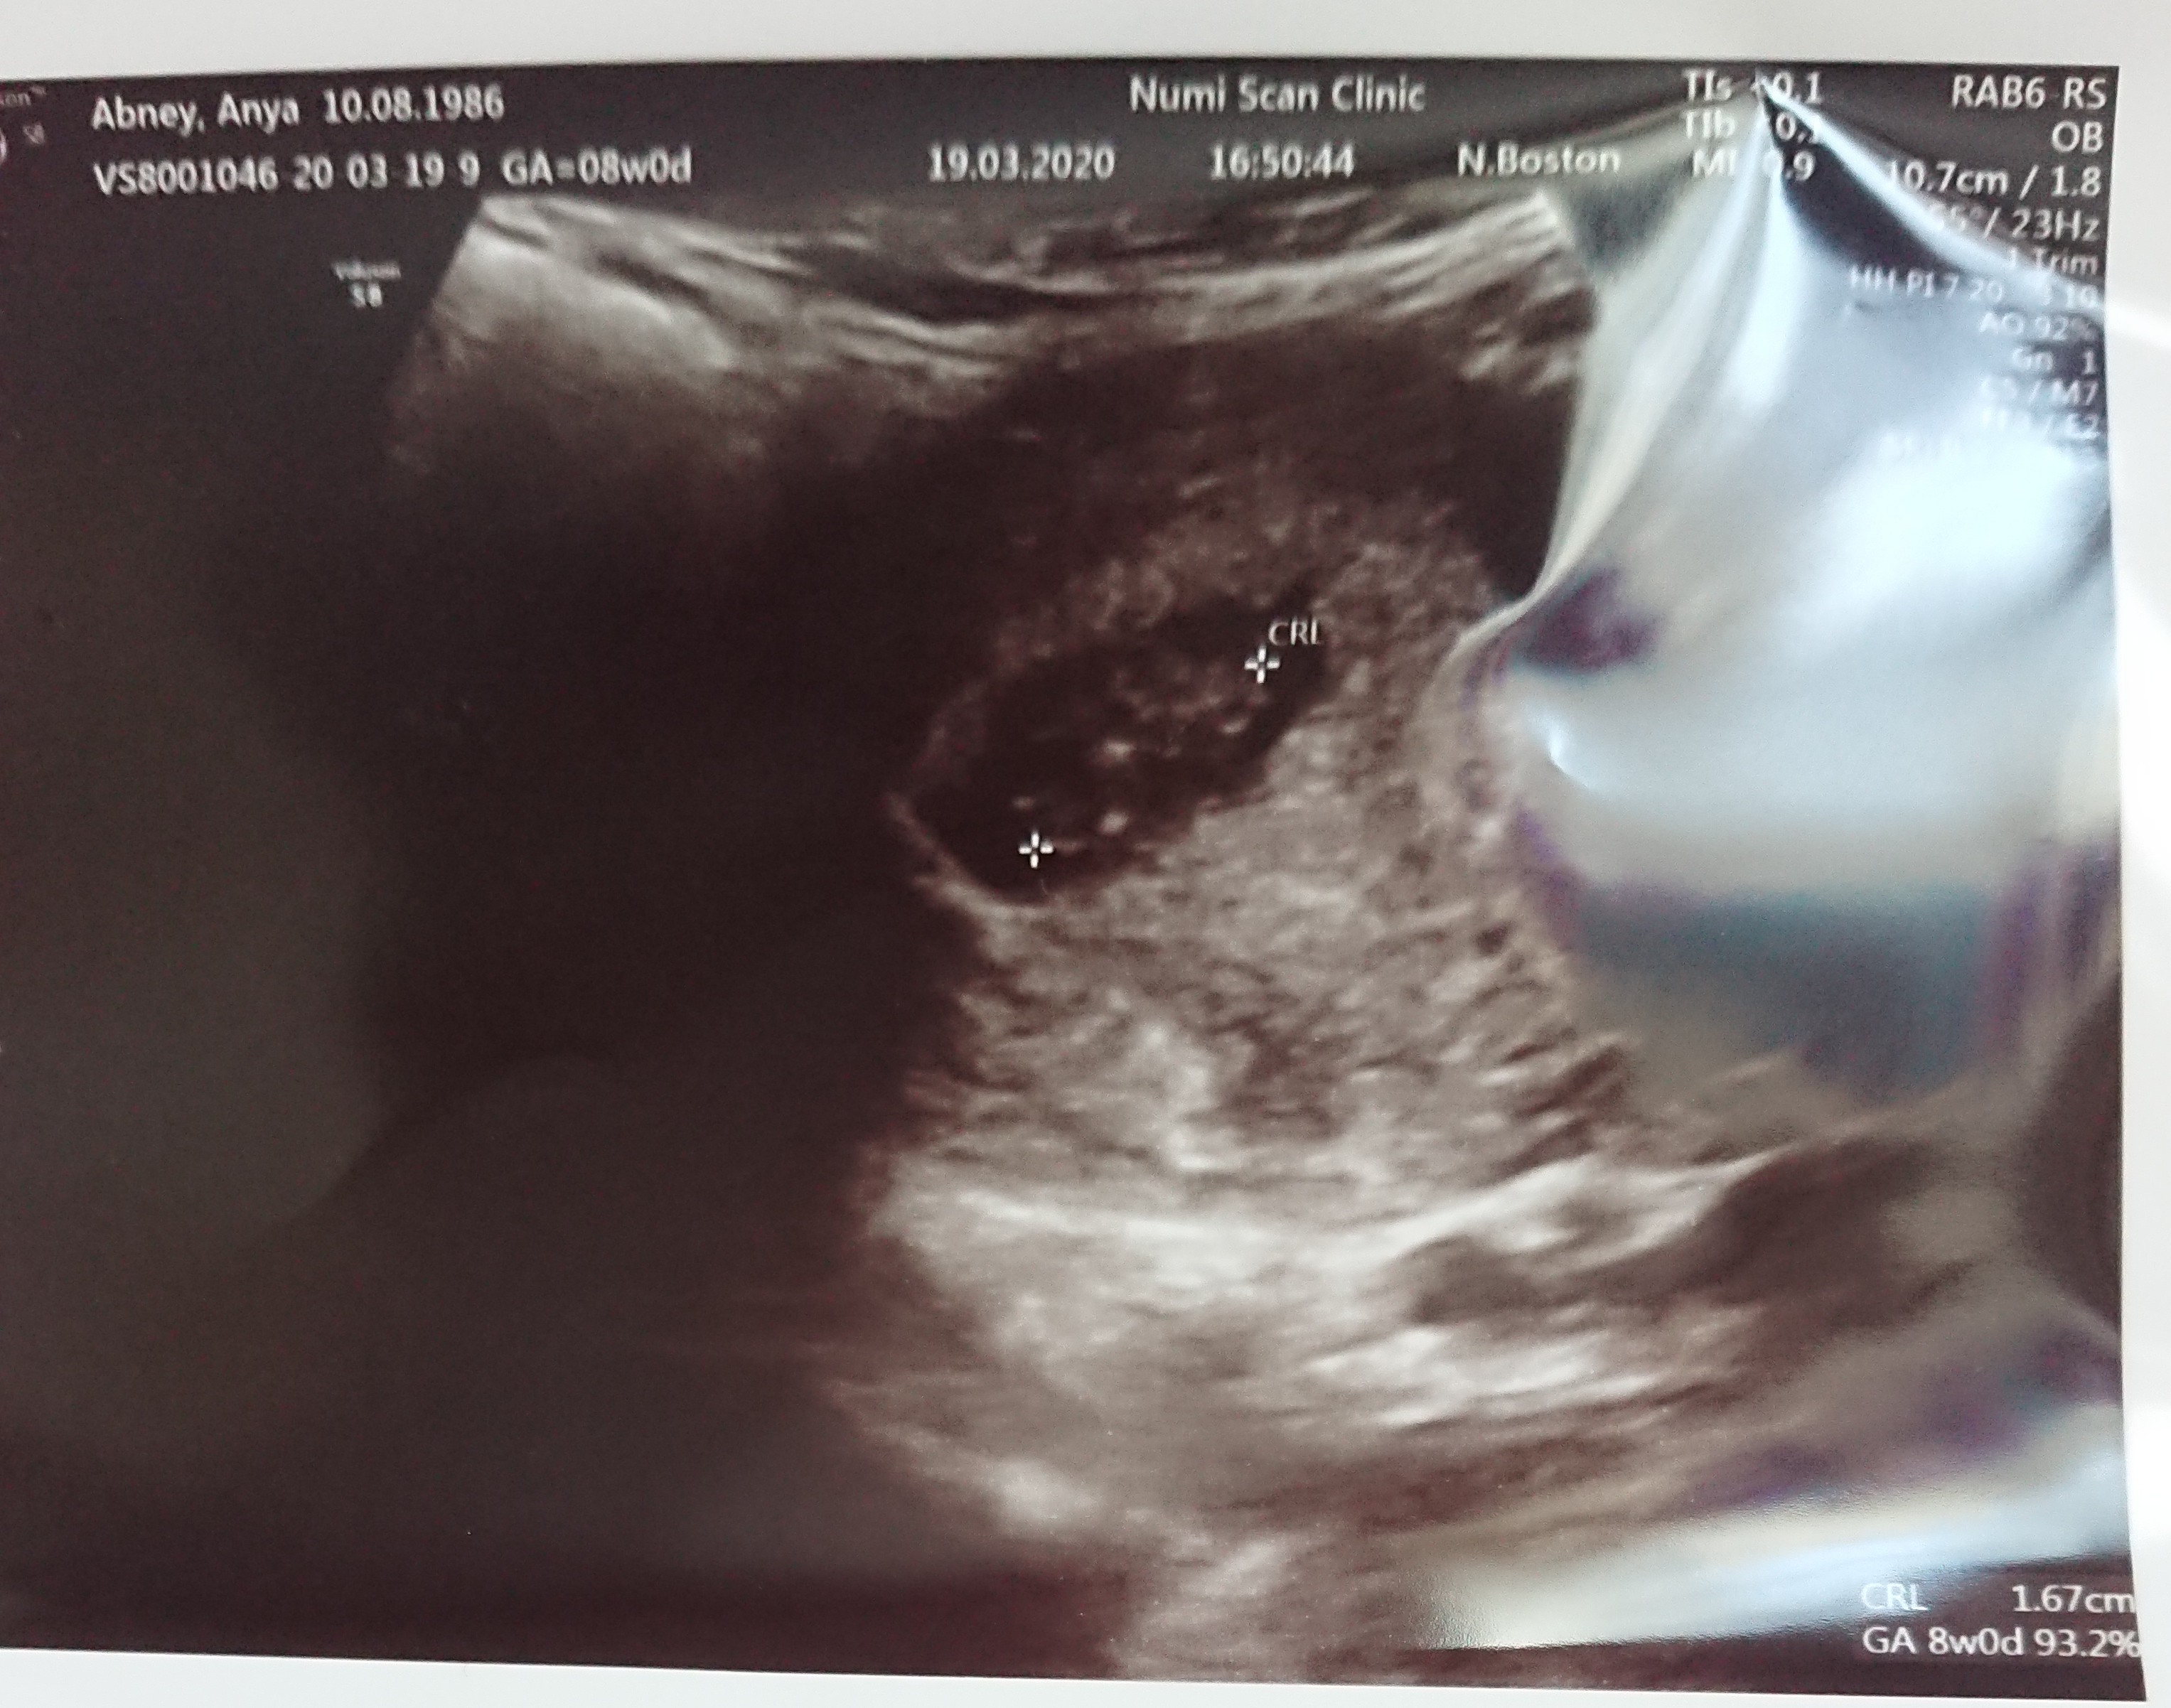

Miałam USG, potem pokaże ale niewiele widać bo podobno nie miałam pełny pęcherz. Czasu też dużo nie było bo mój syn dobierał się do rzeczy lekarza... Ten próbował go zagadać i pyta czy wiesz kto to jest na monitorze.. A mój Albert mówi że to coronavirus... 🙈🤦🏼‍♀️

Chciałam przedstawić moje niewidzialne dziecko...podobno wina niepelnego pęcherza...